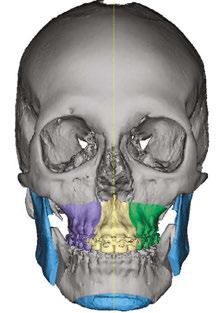

The purposes of the face, in hierarchal order, are 1) breathing, 2) eating, and 3) communicating. The brain prioritizes these purposes by causing all parts of the facial system to work together towards the three goals. When growth is inappropriate, the brain compensates to accomplish the purposes of the face often at the expense of the parts (fascia, muscles, teeth, joints, spine, etc.) These compensations may cause dysfunction, deformation, and destruction (Figures 1-4). Knowing the purposes of the face allows us to define the healthiest place for each individual part of the face. It is that position that minimizes energy expenditure as that part engages and relates with other parts in helping the face to breathe, eat, and communicate.

Figure 1 (left): A photo of a 69-year-old woman with a 2 mm anterior open bite and an excessive interlabial gap of 9 mm. Figure 2 (right): The sagittal slices of the above patient’s mandibular condyles reveal discontinuity of the cortical outline at the fossa and condyle (erosions). The altered condyles are flat along their path of function when she pushes her lower jaw forward to get the lips to touch in speaking, chewing, and breathing through her nose. Image captured using Dolphin® software (www.dolphinimaging.com)

Figure 3 (left): This same 69-year-old has undergone orthognathic surgery (bilateral sagittal split osteotomies and genioplasty) to close her open bite and shorten her anterior face height. This allows her lips to touch at rest and reduces energy usage to breathe, eat, and communicate. Figure 4 (right): The energy reduction at the mandibular condyles allows them to heal as evidenced by the recortication of the bone with the disappearance of the bony erosions. Image captured using Dolphin software (www.dolphinimaging.com)